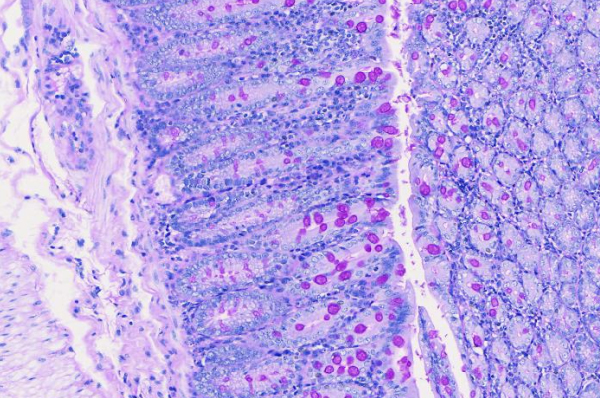

pas

院校/单位:广州市粤斌医学研究有限公司

样本种属:小鼠

组织名称:

实验日期:2024-08-20